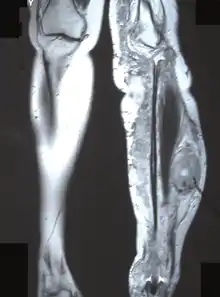

The most conclusive test for a patient with a potential neurofibrosarcoma is a tumor biopsy (taking a sample of cells directly from the tumor itself). MRIs, X-rays, CT scans, and bone scans can aid in locating a tumor and/or possible metastasis.